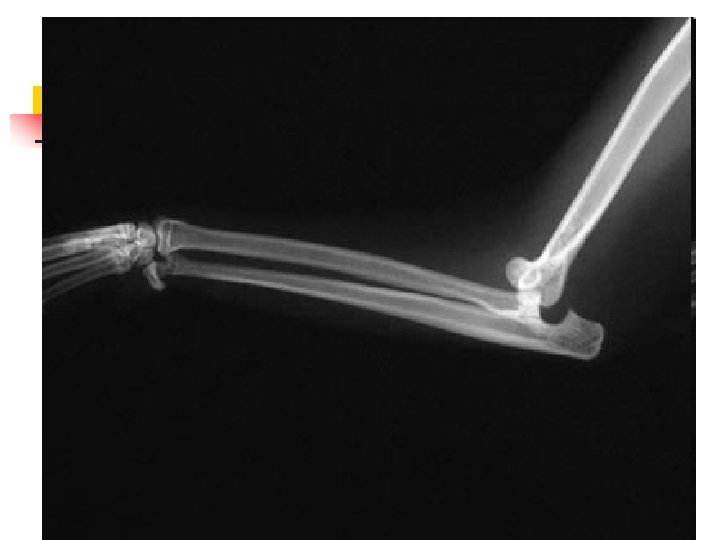

When Animals Limp n n n The good new is that 9 out of 10 limping animals have what we call soft tissue injuries a sprain, a pull, a bruise and only require exercise restriction to heal. However, 1 out of 10 animals with lameness has something more serious, and we can tell which ones by close observation of the patient walking and careful physical examination. In those cases, radiographs are used to make a diagnosis.

When Lameness isn’t Simple n n Sometimes when an animal limps the cause turns out to be something more serious than a simple injury. The doctors palpated a firm, painful lump in the leg this dog was favoring. Radiographs showed that the bone was expanded in that area, with a motheaten, hollowed-out center. These are classic signs of a tumor in the bone, known as an osteosarcoma.